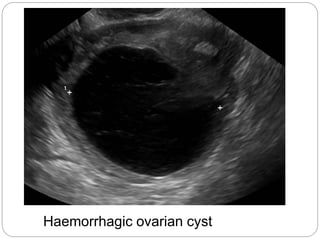

Haemorrhagic ovarian cyst

 Both follicularand luteal cysts could become haemorrhagic if bleeding occured within them leading to rapid increase in size and severe pain.  they might cause severe pain only if they are large in size (>7 cm) and cause pressure symptoms or torsion of the whole ovary compromising blood flow when surgical intervention is indicated

A simple ovariancyst on the right side of the uterus